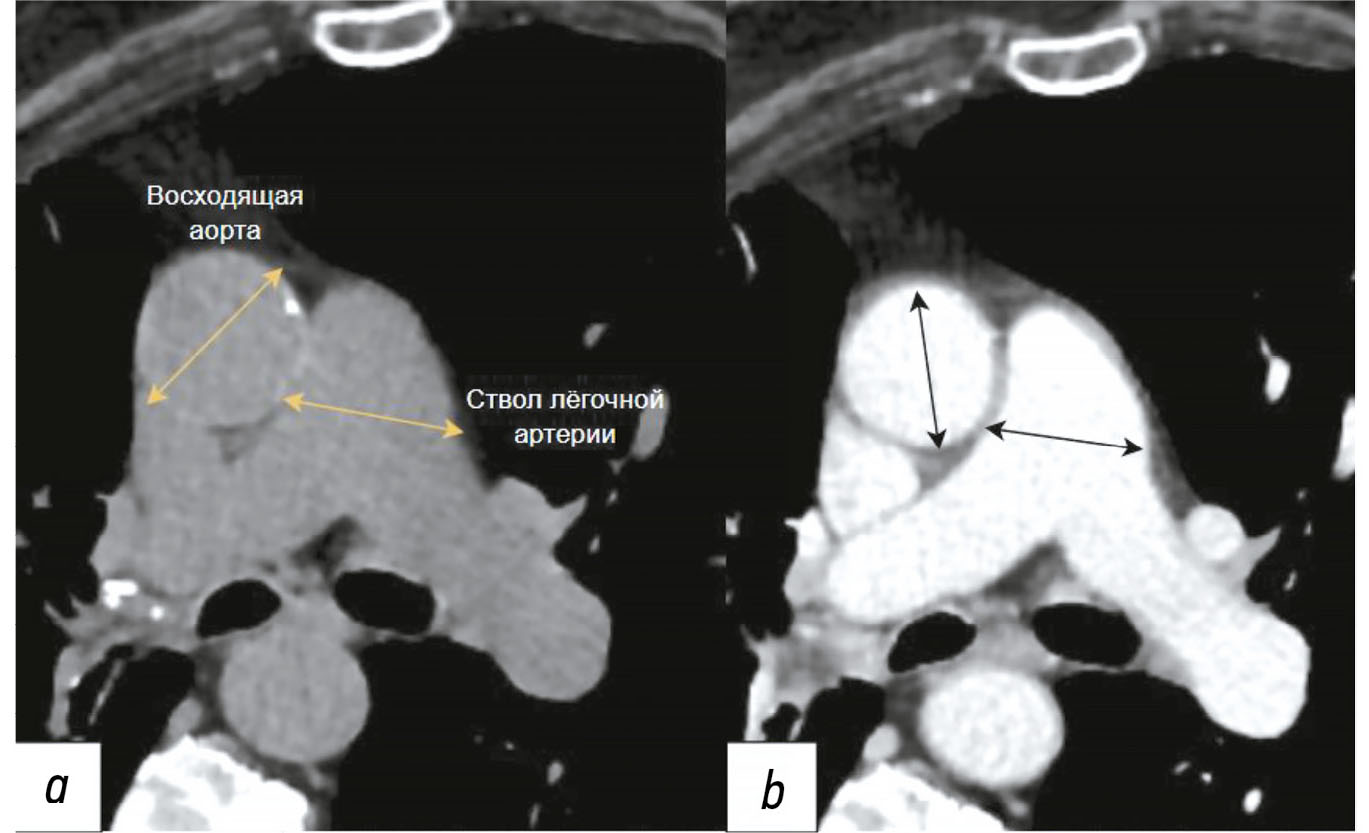

Diagnosis of thoracic aortic aneurysms and pathological pulmonary trunk dilation using chest computed tomography and artificial intelligence: modern approaches and prospects (a review)

Abstract

Early diagnosis of thoracic aortic aneurysms and pathological pulmonary trunk dilation is crucial to prevent severe complications, including vascular wall rupture and acute right ventricular failure, and reduce cardiovascular mortality. This review examines contemporary imaging approaches for these conditions, focusing on computed tomography as the gold standard modality. Emphasis was placed on the implementation of artificial intelligence technologies, which enable automatic segmentation of vascular structures, measurement of their diameter, and opportunistic screening, allowing early detection of asymptomatic conditions without additional diagnostic procedures, thereby reducing radiologist workload and improving medical care quality. The study comprehensively analyzed the Moscow Experiment, wherein the application of artificial intelligence in medical image analysis showed high sensitivity, reproducibility, and reduced reporting time. Despite these significant advantages, the need for expert supervision of artificial intelligence-generated results to ensure diagnostic accuracy and reliability is emphasized. Moreover, the review highlights the importance of adapting algorithms to different scanning protocols and population-specific features. Additionally, the importance of interdisciplinary collaboration among cardiologists, radiologists, data scientists, and software developers for the effective integration into routine clinical practice is pointed out. Therefore, the review outlines the potential of artificial intelligence technologies to enhance diagnostic quality and underscores the need for further clinical research and standardization of methods for successful integration into daily practice.